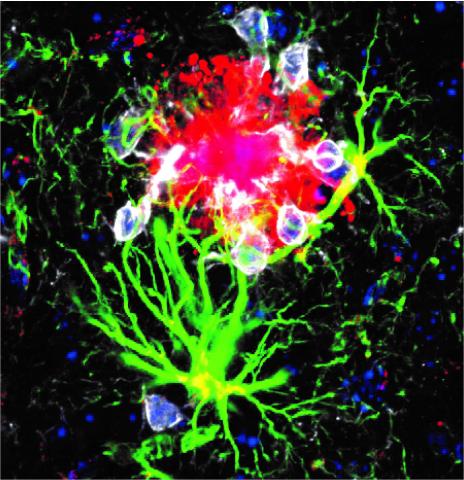

They found that microglia sensed changes happening in blood immune cells, called neutrophils, that are first responders to fight off bacteria and pathogens. This was particularly true for female brains with APOE4 before any signs of cognitive decline. Such findings suggested that APOE4 puts women at greater risk for Alzheimer’s because it triggers changes in neutrophils in the blood, which are then picked up by microglia in the brain.

Microglia are not just brain sensors, they are also the janitors responsible for clearing amyloid plaques, Dr. Rosenzweig explains. “Microglia that are healthy should [clean up plaques] and resolve the inflammation quickly. But what happens in Alzheimer’s is this process is impaired, and microglia fail to respond to neurodegeneration and to those plaques.”

The damage to brain cells caused by plaques instigates a change in microglia. These immune cells go from a calm, peace-keeping state to a disease-fighting inflammatory response. In their prolonged attempt to remove plaques, the microglia generate chronic, damaging inflammation that will eventually prevent them from clearing plaques altogether.

“What we found is a mechanism by which those neutrophils make microglia worse,” she continued. The study findings illustrate a communication pathway in APOE4 carriers by which neutrophils release an inflammatory factor, called interleukin-17F, that interacts with a protein on the surface of microglia to suppress their ability to remove plaques. This negative interaction is unique to APOE4 carriers—and especially strong for women.